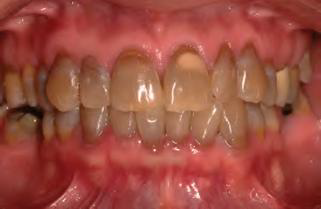

Eruption cyst (EC) | Dentigerous 萌發 | 12a, 12b, 34a, ?6 | 10y ↓ | 藍色或紫棕色 ![]() ![]() |